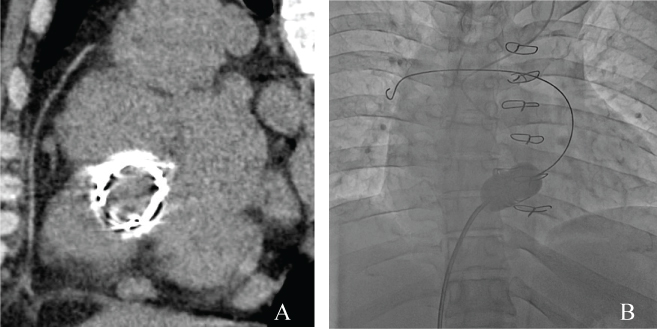

A 38-year-old male presented with right-side heart failure, with symptoms that included dyspnea on exertion, leg edema, and pleural effusion. Soon after birth, he had been diagnosed with incomplete atrioventricular septal defect. At two years of age, a surgical primum atrial septal defect closure, mitral valve plasty, and tricuspid valve plasty were performed. Because he developed severe tricuspid regurgitation at the age of five, a tricuspid valve replacement with a mechanical prosthetic valve (SJM27 mm) was performed. At the age of 20, stuck-valve and severe tricuspid stenosis occurred, and he underwent a second tricuspid valve replacement with a bioprosthetic valve (CEP27 mm). During surgery, an expansive pannus was observed. At the age of 29, the patient ceased medical follow-up. On admission, his physical examination revealed moderate edema in both legs. A Levine Grade III/VI, diastolic rumble also was auscultated at the lower left sternal border. A transthoracic echocardiogram revealed severely calcified, thickened, and immobile leaflets of the bioprosthetic tricuspid valve (Figure 1A, Movie 1). The peak velocity was 2.5 m/sec with a mean diastolic gradient across the tricuspid valve of 14 mmHg (Figure 1B). Tricuspid regurgitation was mild. An invasive hemodynamic study by cardiac catheterization revealed 9.8 mmHg of mean transvalvular pressure gradient and mean right atrial pressure that had elevated to 17 mmHg. The tricuspid valve area was measured as 1.0 cm2 by Gorlin's equation (Figure 2A). He also had two major comorbidities. The first was hepatic cirrhosis due to the hepatitis B virus and a congestive liver; the second was a progressive post-mediastinum tumor, the size of which was 50 × 55 mm. His fourth sternotomy was considered a high-risk procedure. His hepatic function also was thought to be insufficient for highly-invasive surgery. Therefore, the patient was offered a percutaneous transcatheter tricuspid balloon valvuloplasty, a less-invasive procedure.

Figure 2: A) Cardiac catheterization revealed 9.8 mmHg of mean transvalvular pressure gradient and mean right atrial pressure that had elevated to 17 mmHg. The tricuspid valve area was measured as 1.0 cm2 by Gorlin's equation; B) After the procedure, mean transvalvular pressure gradient decreased to 5.3 mmHg, mean right atrial pressure was then reduced to 15 mmHg and the tricuspid valve area increased to 1.3 cm2. View Figure 2

A 14-Fr long sheath was inserted via the right femoral vein and the guide wire passed through the bioprosthesis to the right pulmonary artery. A 26 mm Inoue balloon (Toray Medical Ltd., Japan) was inflated to a maximum of 26 mm, equivalent to 96% of the bioprosthetic valve (Figure 3A and Figure 3B). After the procedure, mean transvalvular pressure gradient decreased to 5.3 mmHg, mean right atrial pressure was then reduced to 15 mmHg and the tricuspid valve area increased to 1.3 cm2 (Figure 2B). The echocardiogram revealed that peak velocity had decreased to 1.7 m/sec, with a mean diastolic gradient of 7.5 mmHg (Figures 1C and Figure 1D, Movie 2). Deterioration of tricuspid regurgitation did not occur.

Figure 3: A) CT image before the valvuloplasty shows a highly calcified bioprosthetic valve in the tricuspid position; B) Fluoroscopic image in the anterior-posterior view shows the stiff guide wire passing through the center of the deteriorated bioprosthetic tricuspid valve, with the wire tip in the right pulmonary artery. A balloon valvuloplasty was performed using an Inoue balloon (maximum diameter 26 mm). View Figure 3